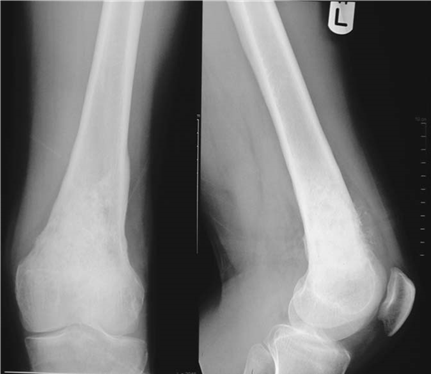

Illustration 8 for Ace FRCS Orthopaedics: Oxford University Press Adult Pathology Viva

๐Ÿ” Click to enlarge

Clinical Radiograph / Orthopedic Image

What implants do you use for revision total knee replacements?

What implant do you use for revision total knee replacements (TKRs)?

[ This question is aimed at exploring your understanding of pre-operative planning based on the individual requirements of the clinical case.] The range of implants or system I use would depend on the clinical situation: primary TKR, post stabilized, super-stabilized, rotating hinge, with stems ยฑ augments, tumour prosthesis. Whenever faced with a revision situation it is also prudent to consider both amputation and arthrodesis as options.

[You are passed a hinged prosthesis.] What are the benefi ts and disadvantages of this type of component?

These implants are used in ligament insuffi ciency and/or cases with major bone loss. The problems with increasingly constrained implants are transmission of high forces across the boneโ€“cementโ€“ implant interface which can lead to premature loosening.

If you where to revise a unicompartmental knee replacement what implant would you choose?

Ideally I would use a primary TKR implant. If there has been some tibial loosening and bone loss, a stemmed implant possibly with augments may be required.

If you had a patient with a posterior cruciate ligament (PCL) sacrifi cing knee with a complete medial collateral ligament disruption and dislocation what implant choice might you make?

Most likely I would require a rotating hinge stemmed system.